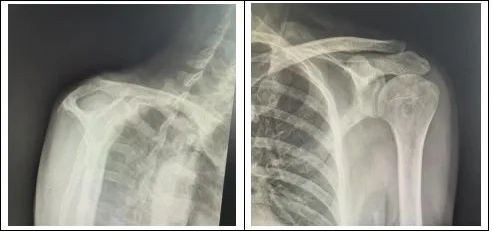

经过团队反复研讨,副主任医师李政为王先生实施了左肩关节松解术,肩袖锚钉缝合术,并在术中使用了双排锚钉。双排锚钉可以提供更强大的稳定性,可以使得肩关节在术后可以进行早期功能锻炼。该手术完美解决了治疗中的矛盾,整个手术过程不过两个小时。